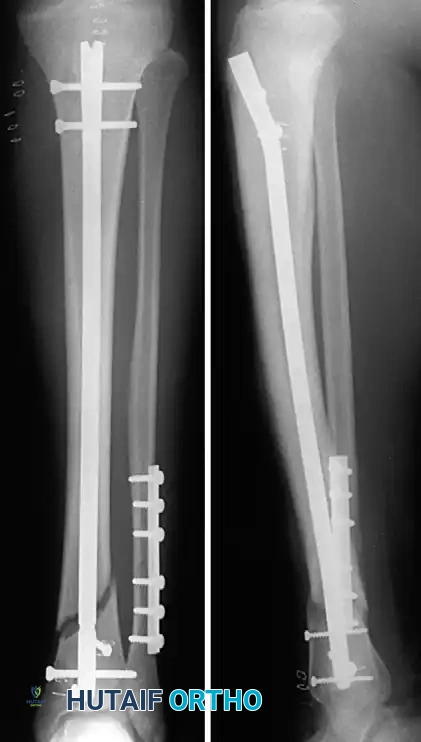

Image

Fig. 8: Final fluoroscopic assessment demonstrating excellent axial alignment following intramedullary nail insertion and static interlocking screw placement.

• Distal Locking: Perform distal locking first using a freehand perfect-circle fluoroscopic technique. Ensure the drill bit passes cleanly through both cortices and the nail hole.

• Proximal Locking: Utilize the outrigger targeting jig to place the proximal locking screws.

• Before placing the final proximal screws, release traction and gently impact the heel to compress the fracture site, eliminating any iatrogenic distraction.